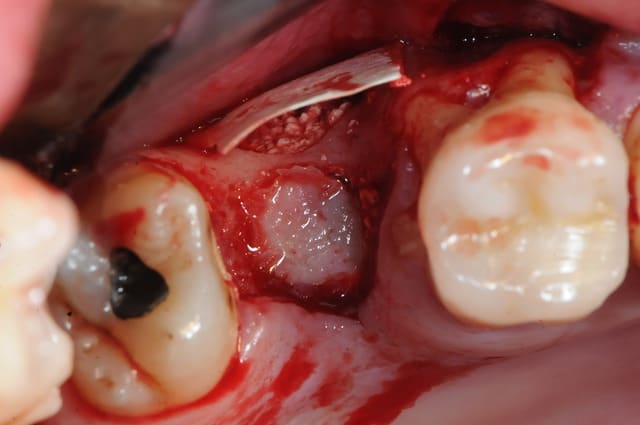

1&2: prélèvement sanguin pour centrifugation et réalisation de membranes de PRF

4: incision décalée en palatin par rapport au trou de la cbs (pas trop car après il y a risque de nécrose)

5: en général, il ya décollement assez facile entre la membrane de schneider et le palais.

1&2 : réalisation à l'aide d'une tréphine de la fenêtre vestibulaire pour aller plus vite et surtout pour pouvoir réutiliser plus tard ce petit bloc osseux.

3: fenêtre et CBS bien visibles

j'aurai aimé faire mon abord latéral plus haut, mais je vous rappel que l'on est au niveau de la 7 et que c'est difficile d'écarter les tissus.

vous noterez tout de suite la différence de teinte entre un sinus sain et avec ici, un sinus hyper inflammatoire et infecté (une vraie cocotte-minute)